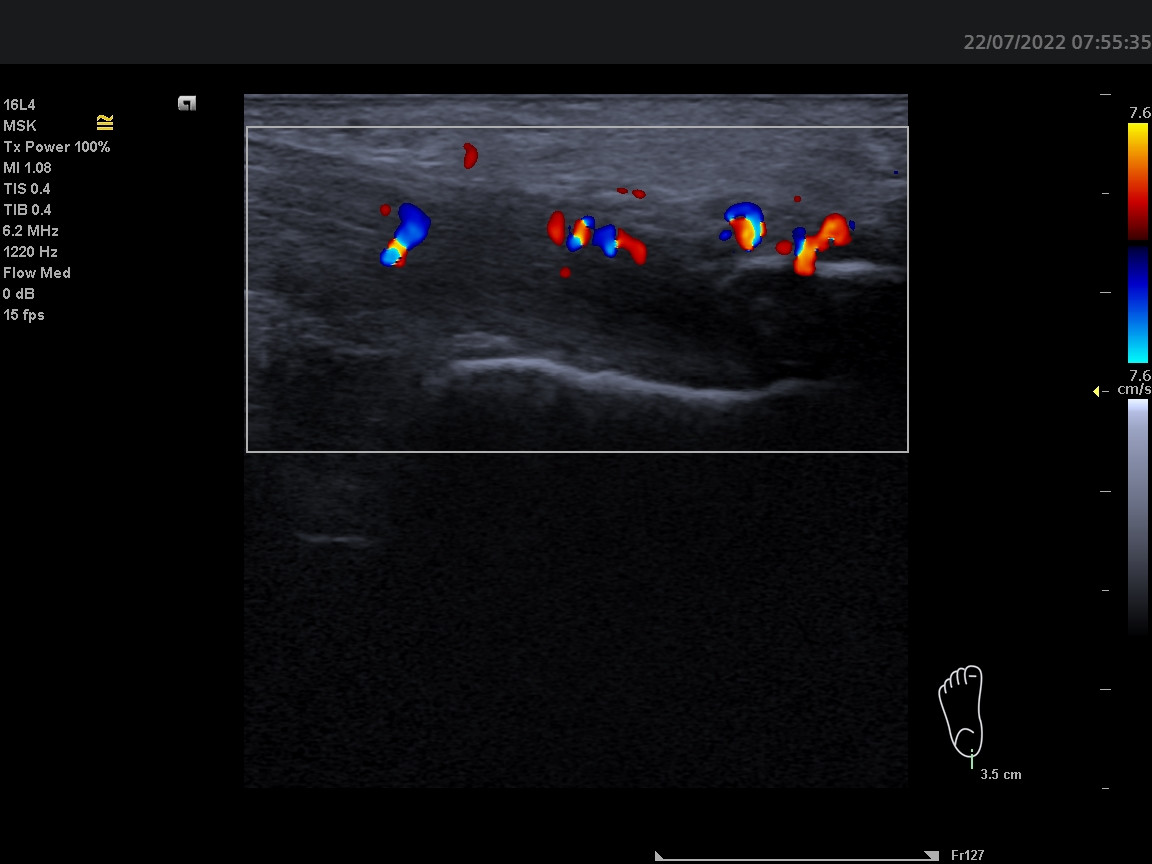

Dobrý den, ortopedem byla odeslána pacientka k revmatologickému vyšetření. 58 let, OA: HT, Psoriasis vulgartis, Asthma, HT, Barretův jícen - disp gastroenterologie. Pacientka si delší dobu stěžuje na úporné bolesti v oblasti úponu levé achillovy šlachy, dle Rtg 01/2022 dorzální i plantární patní ostruha - léčena ozařováním bez efektu. Sonograficky potvrzuji masivní patní ostruhu s mohutnými splývajícímí dopplerovskými signály v okolí i dále proximálně. Otázka: lze při této konstelaci výsledků odlišit primární psoriatickou entezitidu se vznikem masivního entezofytu od primární idiopatické patní ostruhy se sekundárním zánětem? Děkuji.

Z prosté zkušenosti mi na těchto snímcích pro jasnou entezitidu chybí hypoechogenita a zduření šlachy v oblasti enteze (zánětlivý projev) a PD signály pod 2mm od úponové kortikalis. Na snímcích chybí měřítko vzdálenosti, toto se tedy pouze domnívám. PD signály jsou ponejvíce okolo entezofytu a v proximálnějších částech šlachy. Tento nález bych hodnotila nejspíše jako tendinitidu Achillovy šlachy a masivní entezofyt, připomínajícím až Haglundovu exostózu.